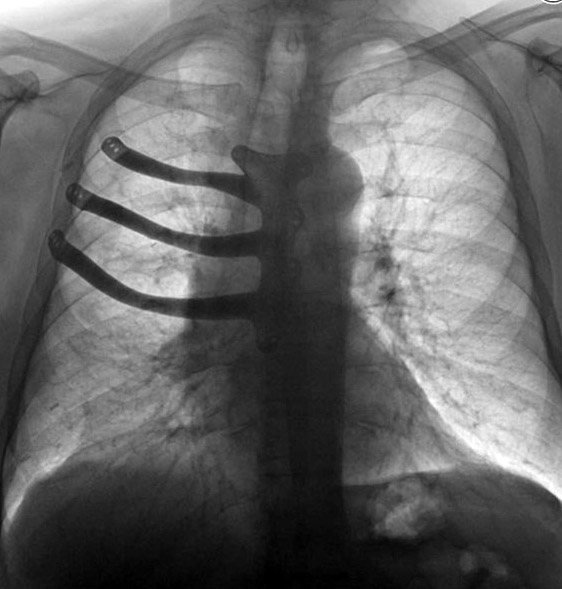

В британском госпитале Моррисон в городе Суонси во время операции по удалению раковой опухоли врачи реконструировали больному грудную клетку с помощью 3D-принтера, передает ВВС.Из-за большого размера раковой опухоли хирургам пришлось удалить 71-летнему Питеру Мэггзу еще три ребра и часть грудной кости. "Это было чревато серьезными повреждениями, способными нарушить работу всей грудной клетки, реконструировать которую было бы очень сложно", - рассказала хирург-кардиолог Айра Голдсмит. По ее словам, протез из медицинского цемента, который обычно отливают хирурги в таких случаях, пришлось бы делать прямо во время операции, одно это могло занять часа полтора. Но у пациента были и другие проблемы, в том числе с сердцем. Поэтому операцию необходимо было закончить как можно быстрее. ![]() Фото: wales.nhs.uk Удаленные кости британские врачи заменили заранее подготовленным титановым имплантатом, который был напечатан на 3D-принтере. В сообщении отмечается, что индивидуальный имплантат из титанового сплава был создан на основе компьютерной томографии пациента. Это один из первых имплантатов, напечатанных в Британии с помощью 3D-принтера. В итоге, 8-часовая операция прошла успешно, пациент говорит, что чувствует себя хорошо. | |